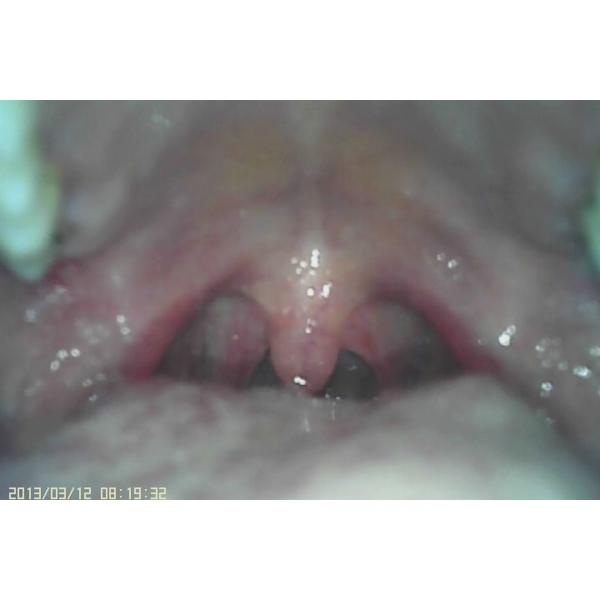

| Объектив Ларынгоскопе | Расмотрите горло |

1. Специально конструированный для отдела ЭНТ. Его можно использовать для того чтобы рассмотреть барабанную перепонку, носовую полость и горло с различным зондом камеры.